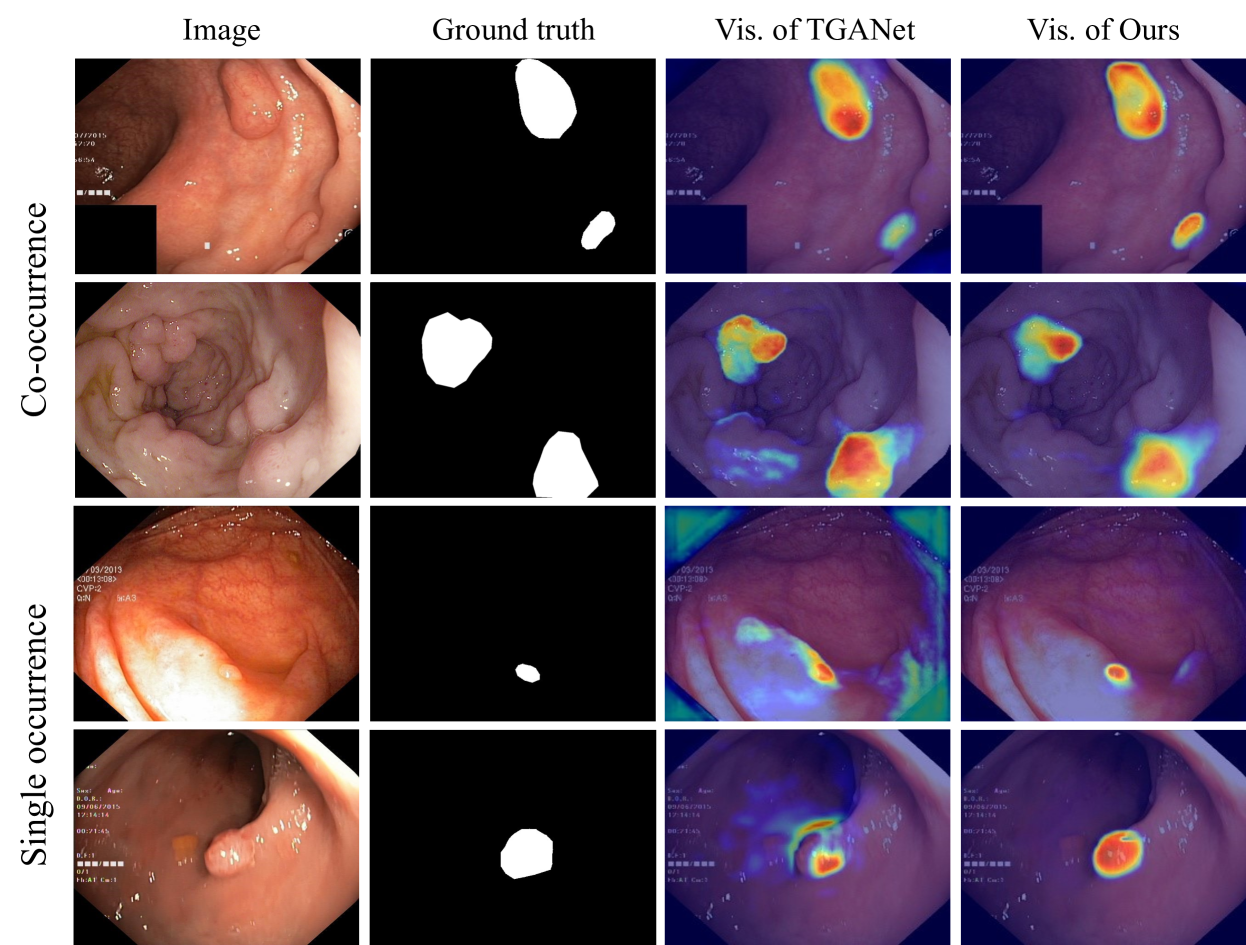

Refer to caption

Figure 3: The Grad-CAM visualization of different methods. It illustrates the attention areas of our model and TGANet in cases of co-occurrence and individual appearances.

Co-occurrence phenomena are widespread in medical imaging, which often cause models to learn incorrect patterns, thus degrading their performance. Figure 3 shows a visual comparison between TGANet (Tomar et al. 2022) and our method on several examples from the Kvasir-SEG dataset (Jha et al. 2020). For both, we utilize Grad-CAM (Selvaraju et al. 2017) to visualize convolutional layers near the output layer, intuitively demonstrating the focus of the models. For co-occurring polyps, both models can achieve accurate localization. However, when the polyp appears alone, TGANet tends to mistakenly predict multiple polyps. In contrast, our method avoids the misleading effects of co-occurrence phenomena. It remains capable of accurately recognizing and segmenting when a single polyp appears. In our framework, we overcome co-occurrence phenomena through the specially designed Contrast-Driven Feature Aggregation module and Size-Aware Decoder, which will be detailed in the following two subsections.